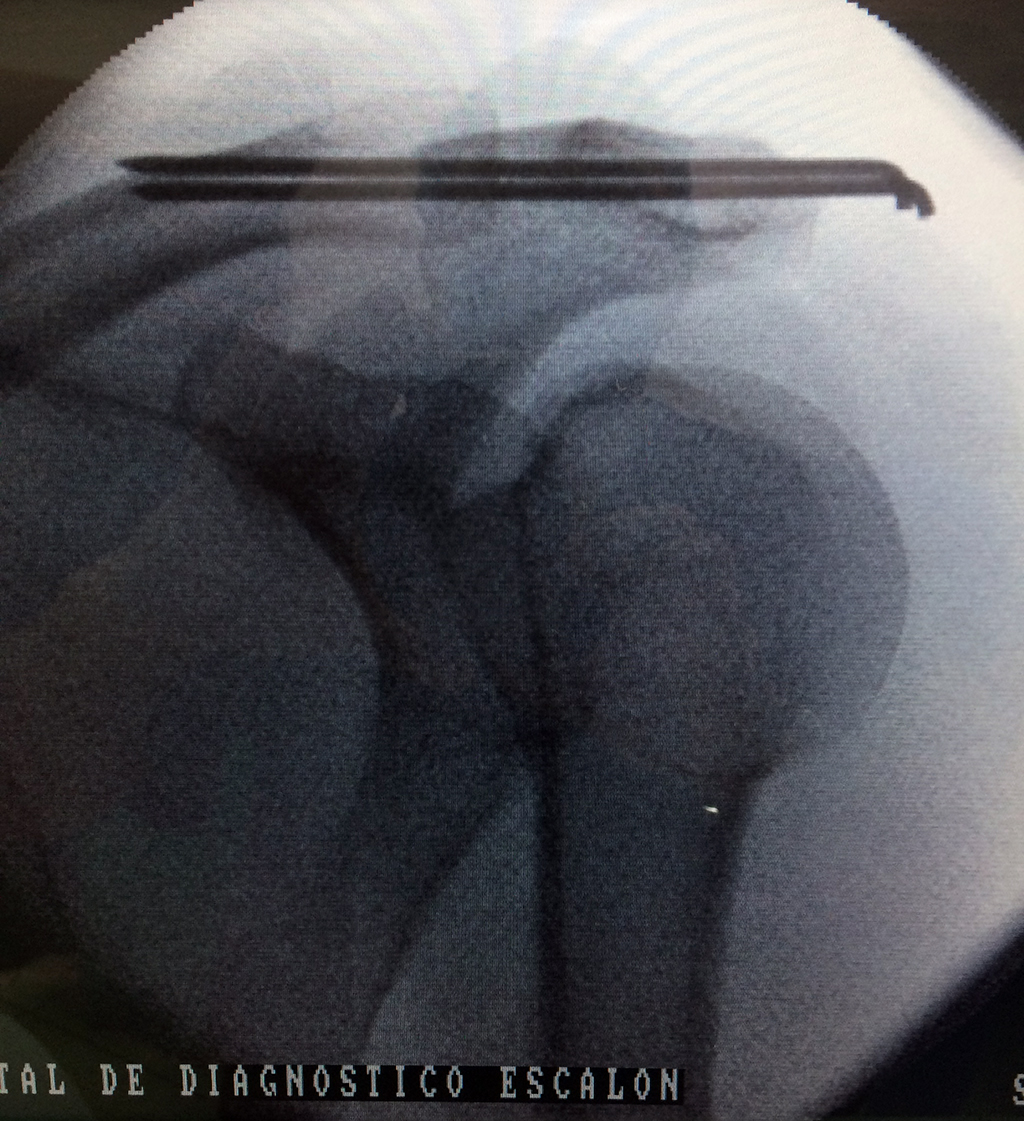

Se considera el único medio de unión entre el miembro superior y el tórax. A pesar de su aspecto, similar al de un hueso largo, posee una estructura semejante a la de un hueso plano, ya que carece de epífisis y de diáfisis, lo que la harían entrar dentro de la clasificación de hueso largo. Carece de un canal medular propiamente dicho.